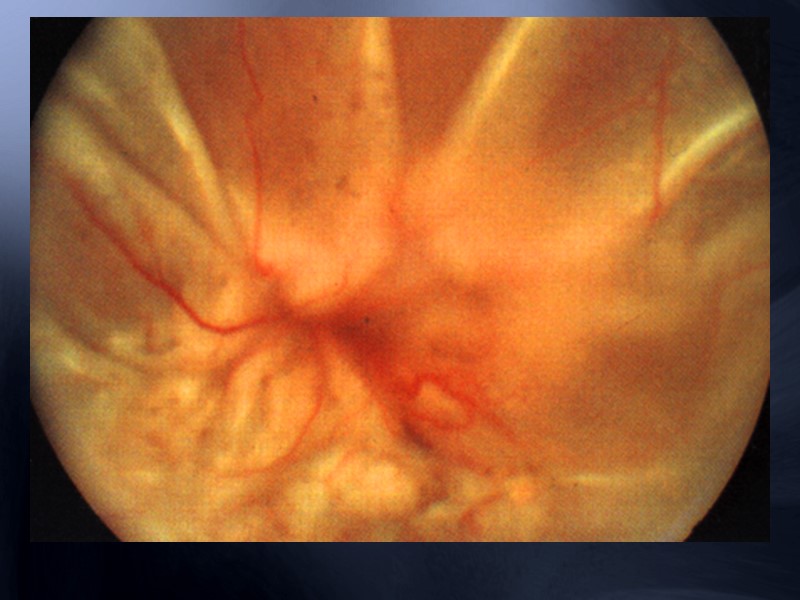

Пролифративная витреоретинопатия - это разрастание аваскулярных фиброцеллюлярных ретинальных мембран, связанных с регматогенной отслойкой сетчатки. Она характеризуется формированием поверхностных мембран в стекловидном теле, на поверхности сетчатки, под сетчаткой и в области цилиарного тела. Контракция этих мембран может вызвать складки сечатки, образование разрывов, рецидивы отслойки сетчатки и гипотонию глаза.

Пролиферативная витреоретинопатия Передняя ПВР Укорочение сетчатки за счёт контракции поверхностных мембран.